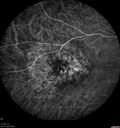

64 year old man. Diagnosed with hemangioma in 2015. PDT in 2016. Images are from 2020 when fluid started to reaccumulate. Needed PDT repeated two more times. PDT treatments: [1] 2/19/2015 -  Pavan (IOP  problem after PDT)  AND [2] 11/2/21 PDT (7 mm temporal to fovea) - SMC  AND [3] 7/22/22 PDT 7.5 mm Temporal to the fovea

Choroidal Hemangioma Requiring PDT repeatedly215 views64 year old man. Diagnosed with hemangioma in 2015. PDT in 2016. Images are from 2020 when fluid started to reaccumulate. Needed PDT repeated two more times.

PDT treatments: [1] 2/19/2015 -  Pavan (IOP  problem after PDT)  AND [2] 11/2/21 PDT (7 mm temporal to fovea) - SMC  AND [3] 7/22/22 PDT 7.5 mm Temporal to the fovea